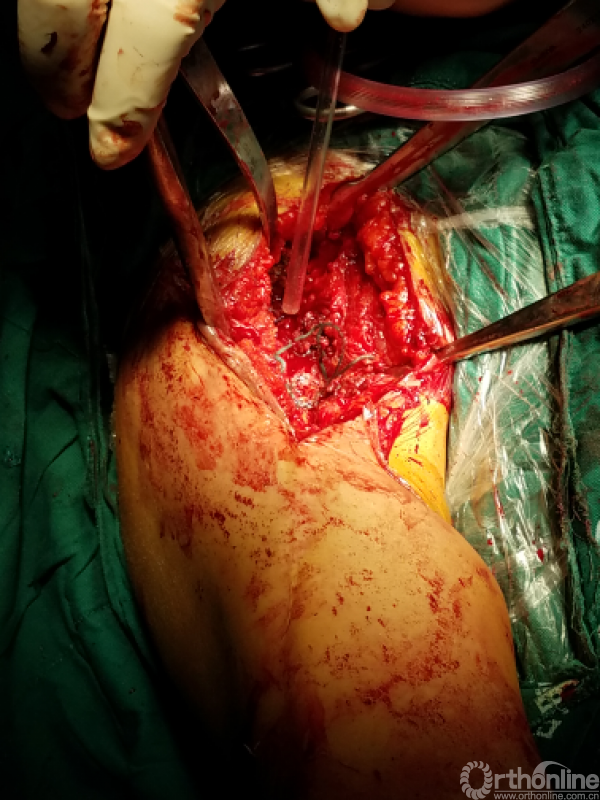

困难重重:

1、广泛粘连,解剖层次不清

2、广泛点状出血灶

3、分不清间隙

4、盂肱关节正常结构位置改变,关节囊瘢痕挛缩替代

5、屈曲外旋看不见关节间隙活动

手术过程:

1.从近端关节前外侧逐步下行,切除瘢痕

2.用食指逐步探查

3.以骨面硬质感为基准从中央部位向两侧分离

4.骨撬,骨膜剥离器协助分离内外侧间隙

5.以缺损处为中心向四周扩大显露

咬出增生骨痂及清理瘢痕组织后显露出原肩袖缝线,杂乱,完整,表面见有脓性组织

瘢痕发硬,变性,周围包裹纤维软骨痂

由于解剖结构紊乱,头静脉已消失。旋肱后动脉,弓状动脉剥离时出血,位于外侧转弯处,行填塞止血。

显露出肱骨头假体柄处

开始向内上扩大显露